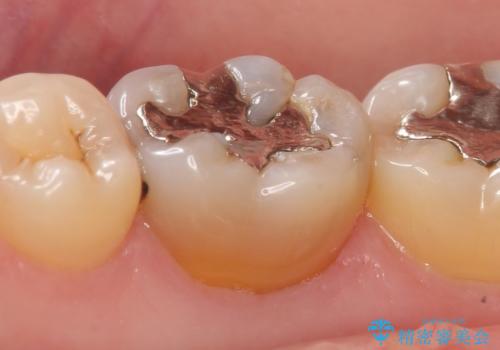

- 右下6番目の歯の舌側に虫歯があるので治療して欲しいといらっしゃった方の症例です。

古い銀歯及び虫歯を除去後、セラミックインレーにて修復を行いました。